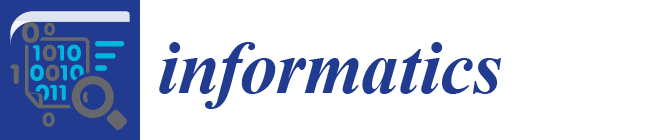

y(t) = yc + a ∙ cost ∙ sinθ − b ∙ sint ∙ cosθ

2.2.2. Ellipse Parameter Estimation

), and the pixel orientation, (

), and the pixel orientation, (  ), vector by means of function Av, which defines the angle between both vectors. The second objective function, f𝑔, Equation (22), aims to find shapes with a higher echogenicity given by the LIP-Sobel gra2-dient, Gv. To avoid the gradient generated by small variations in the intensity of the image, a threshold scheme is utilized. The function is set to the gradient if the threshold is higher than a defined value; otherwise, a penalization is applied to avoid the discontinuity in the shape of the ellipse and the gradient map. The third objective function, fb, Equation (23), acts in a similar way as the previous one, but in this case, a binary map, Bv, is used. Finally, the fourth objective function, fFRS, Equation (24), will guide the ellipse into the center of the artery using the FRS map. Once all the objective functions have been defined, the fitness function can be expressed as shown in Equation (25), where the weights, α1,α2,α3,α4, are incorporated for each respective objective function. After empirical tests, it was found that those values fixed to α1 = 100, α2 = 2, α3 = 100, α4 = 30 of the proposed method achieve satisfactory results.

), vector by means of function Av, which defines the angle between both vectors. The second objective function, f𝑔, Equation (22), aims to find shapes with a higher echogenicity given by the LIP-Sobel gra2-dient, Gv. To avoid the gradient generated by small variations in the intensity of the image, a threshold scheme is utilized. The function is set to the gradient if the threshold is higher than a defined value; otherwise, a penalization is applied to avoid the discontinuity in the shape of the ellipse and the gradient map. The third objective function, fb, Equation (23), acts in a similar way as the previous one, but in this case, a binary map, Bv, is used. Finally, the fourth objective function, fFRS, Equation (24), will guide the ellipse into the center of the artery using the FRS map. Once all the objective functions have been defined, the fitness function can be expressed as shown in Equation (25), where the weights, α1,α2,α3,α4, are incorporated for each respective objective function. After empirical tests, it was found that those values fixed to α1 = 100, α2 = 2, α3 = 100, α4 = 30 of the proposed method achieve satisfactory results.